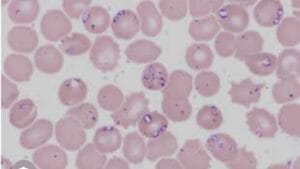

- Analize laborator (hematologie, biochimie, ex urnina, teste)

ANALIZE LABORATOR

ANALIZATOR IMUNOFLUORESCENT VCHECK

Analize cantitative precise obtinute prin metode imunofluorescentei.Este posibila diagnosticarea unor afectiuni cum ar fi boli inflamatorii,pancreatita,afectiuni endocrine.

#CRP-proteina C reactiva,#SAA-amiloidul seric.#cPLlipaza specifica pancreatita canina,#fpl-lipaza specifica pancreatita felina,#cCortizol,#T$,TSH,#Progesteron,markeri cardiaci ==proBNP,#troponina

#Vcheck RDT-interpretare cantitativa teste rapide